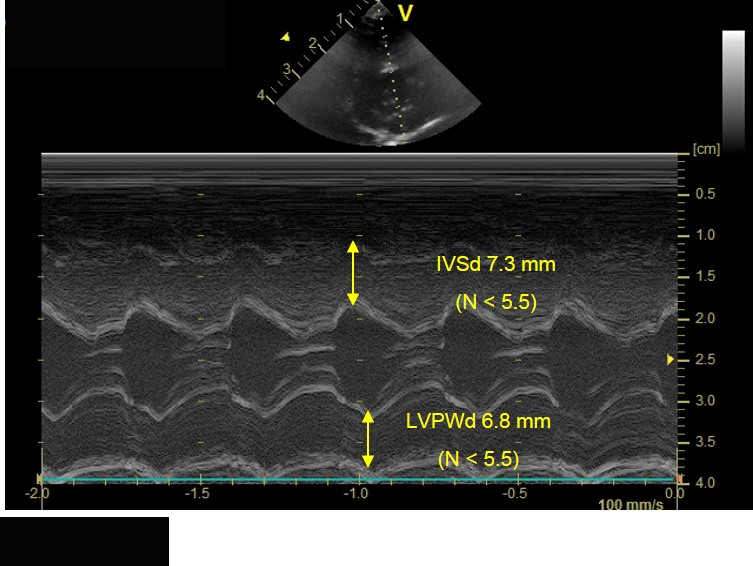

Be wary of fractional shortening! A canine echocardiogram walkthrough

Be wary of fractional shortening! A canine echocardiogram walkthrough Fractional Shortening Echo Normal Range fractional shortening is a measure of how well the left ventricle is contracting itself and therefore reduces the size during systole:. normal values for aorta in 2d echocardiography. Take two orthogonal views (apical four chamber and apical two chamber) ⇒ trace around endocardial border at the end of. Adjustment refers to adjusting for body surface area (bsa). . Fractional Shortening Echo Normal Range.